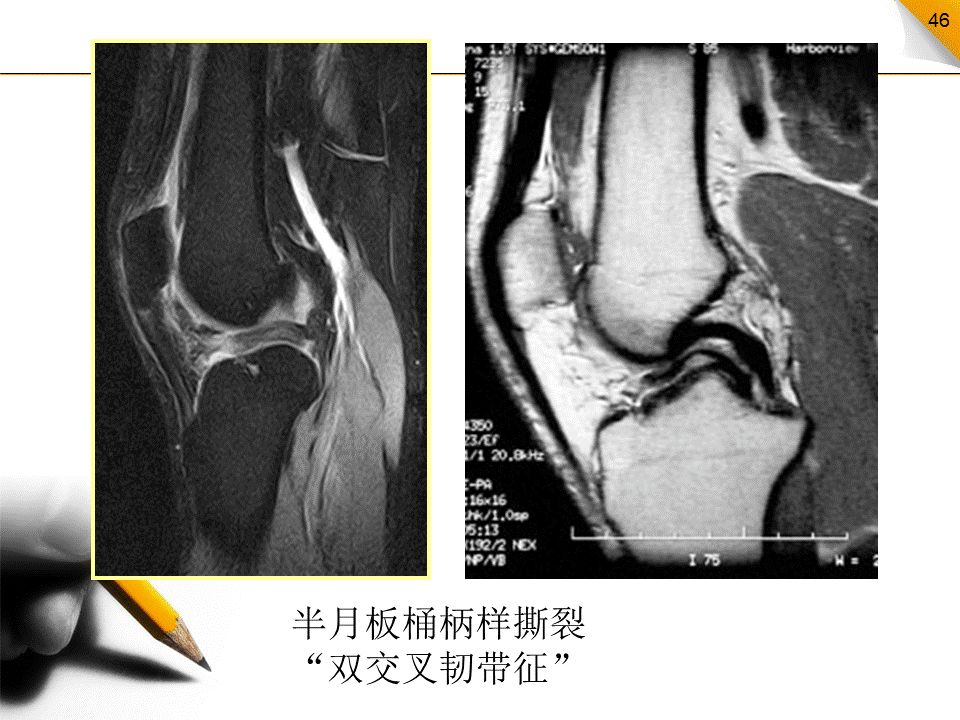

桶柄样撕裂

为纵行撕裂的一个特殊类型。半月板纵行破裂后,其内侧片段发生移位类似于桶的柄,而未移位的外侧片段为桶。多见于内侧半月板,多见于严重外伤所致的年轻患者中。

桶柄样撕裂的MR表现

半月板的宽度减小,同时可见半月板内移矢状面显示残余的前角或后角变小或截断,信号有或无增高矢状面上出现“双前交叉韧带征”或“双后交叉韧带征”。冠状面在髁间窝内有低信号的半月板组织位于交叉韧带旁。